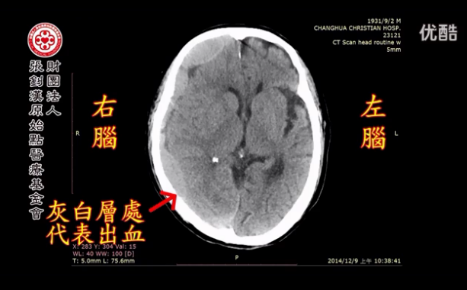

去年2014年10月20日,头部撞了肿起来,还有一点擦伤流血,本来以为是擦一擦就可以好了,但是经过了一个多月,感觉到行动有一点奇怪,一点异常,走路也不稳,所以感觉到各方面都有一点异常变化,可以感觉到这个可能是有一点问题,去做头部的断层扫描,结果发现是颅内还在流血(见下图),